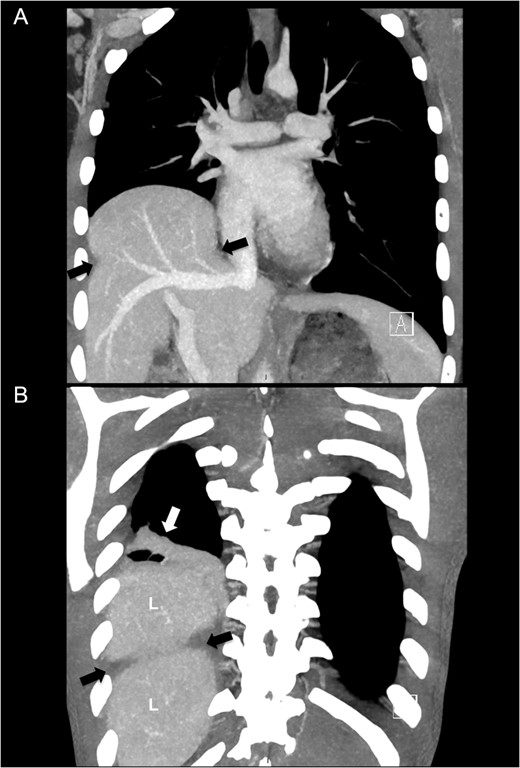

An adolescent male suffered a high-velocity fall while exercising ski-sports in the Alps. He suffered a severe blunt injury with temporary loss of consciousness and was brought to a local hospital where initial work-up and imaging showed no head injury other than a concussion, a right-sided pulmonary contusion with haematothorax and a grade II liver laceration involving segment 8. A right-sided chest drain was placed (Fig. 1) and was kept for several days with strict bed rest and monitoring under conservative management. After 14 days, he eventually was deemed fit for ground-ambulance transfer to our hospital. The chest drain was removed 4 days prior to departure.

Initial chest X-ray after placement of thoracic drain. White arrows note a high-stand of the right diaphragm, black arrow points to chest drain.

On admission after transfer to our hospital he had stable vital signs, with none or little complaints or symptoms. The transferred radiological images from the primary hospital were reviewed and gave immediately suspicion of additional pathology in the right hemithorax, based on a prominent right-sided high-stand of the diaphragm (Fig. 1). A CT scan was made showing a grade II liver laceration and a herniated liver through a large right-sided defect of the right diaphragm (Fig. 2A and B).